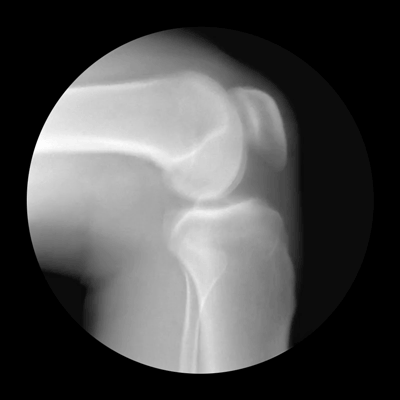

关节僵硬

关节是骨骼之间的连接点,一旦关节出了问题,人的行动力就会受限,久之人就垮了。

关节不好的患者,对心血管系统、呼吸系统、骨骼肌系统等会造成一定影响。因关节病长期卧床的老年人,也会引发骨质疏松、褥疮、消化系统疾病。

关节在生活中最怕几个字:

怕老

随着年龄的增长,人体软骨营养缺乏,骨骼中的无机物增多,骨骼弹力与韧性减低,易导致关节软骨和骨退行性病变。

怕胖

体重增加,下肢关节承重的压力也会增加,引起体位、步态变化,改变关节的生物力学,发生膝内翻或膝外翻,也就是常说的“O”形腿或“X”形腿。

怕伤

在运动、出行的过程中,如果出现急性外伤,一定要及时去医院治疗,以免留下后遗症。

不及时治疗或充分休息,容易留下病根,比如“习惯性崴脚”。

怕勤

关节用得太狠,容易导致机械磨损,破坏软骨。

频繁爬山、爬楼等是非常伤害关节的。建议大家平时通过慢跑、游泳锻炼,既不损伤关节又能锻炼。

怕冷

关节受凉会引起疼痛,易导致关节僵硬。